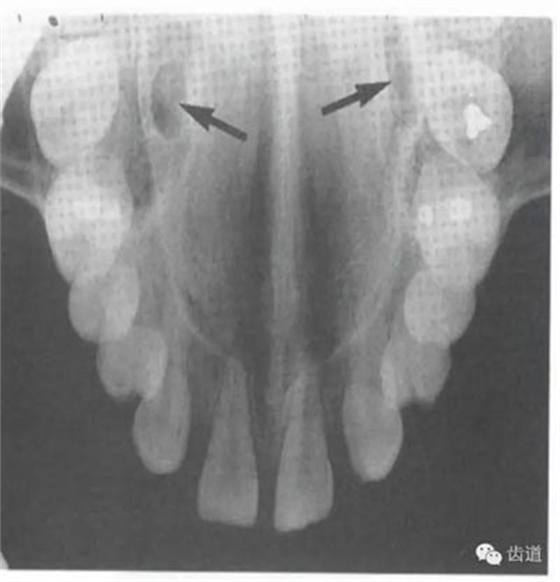

1)頦棘:

位于兩下中切牙根尖下方,下頜骨正中聯(lián)合處顯示為小圓形密度高的影像,在中心有點(diǎn)狀密度低的影像,其周圍骨小梁稀少,為骨松質(zhì)區(qū)。

2)營(yíng)養(yǎng)管:

常見(jiàn)于下頜前牙區(qū),在牙根之間的牙槽骨內(nèi)并與牙長(zhǎng)軸平行的密度低的條狀影像。此為小血管進(jìn)入牙槽突的影像。

在正中聯(lián)合的兩旁,各有一致密影像帶,呈八字形延長(zhǎng)至前磨牙區(qū),是頦嵴的影像。